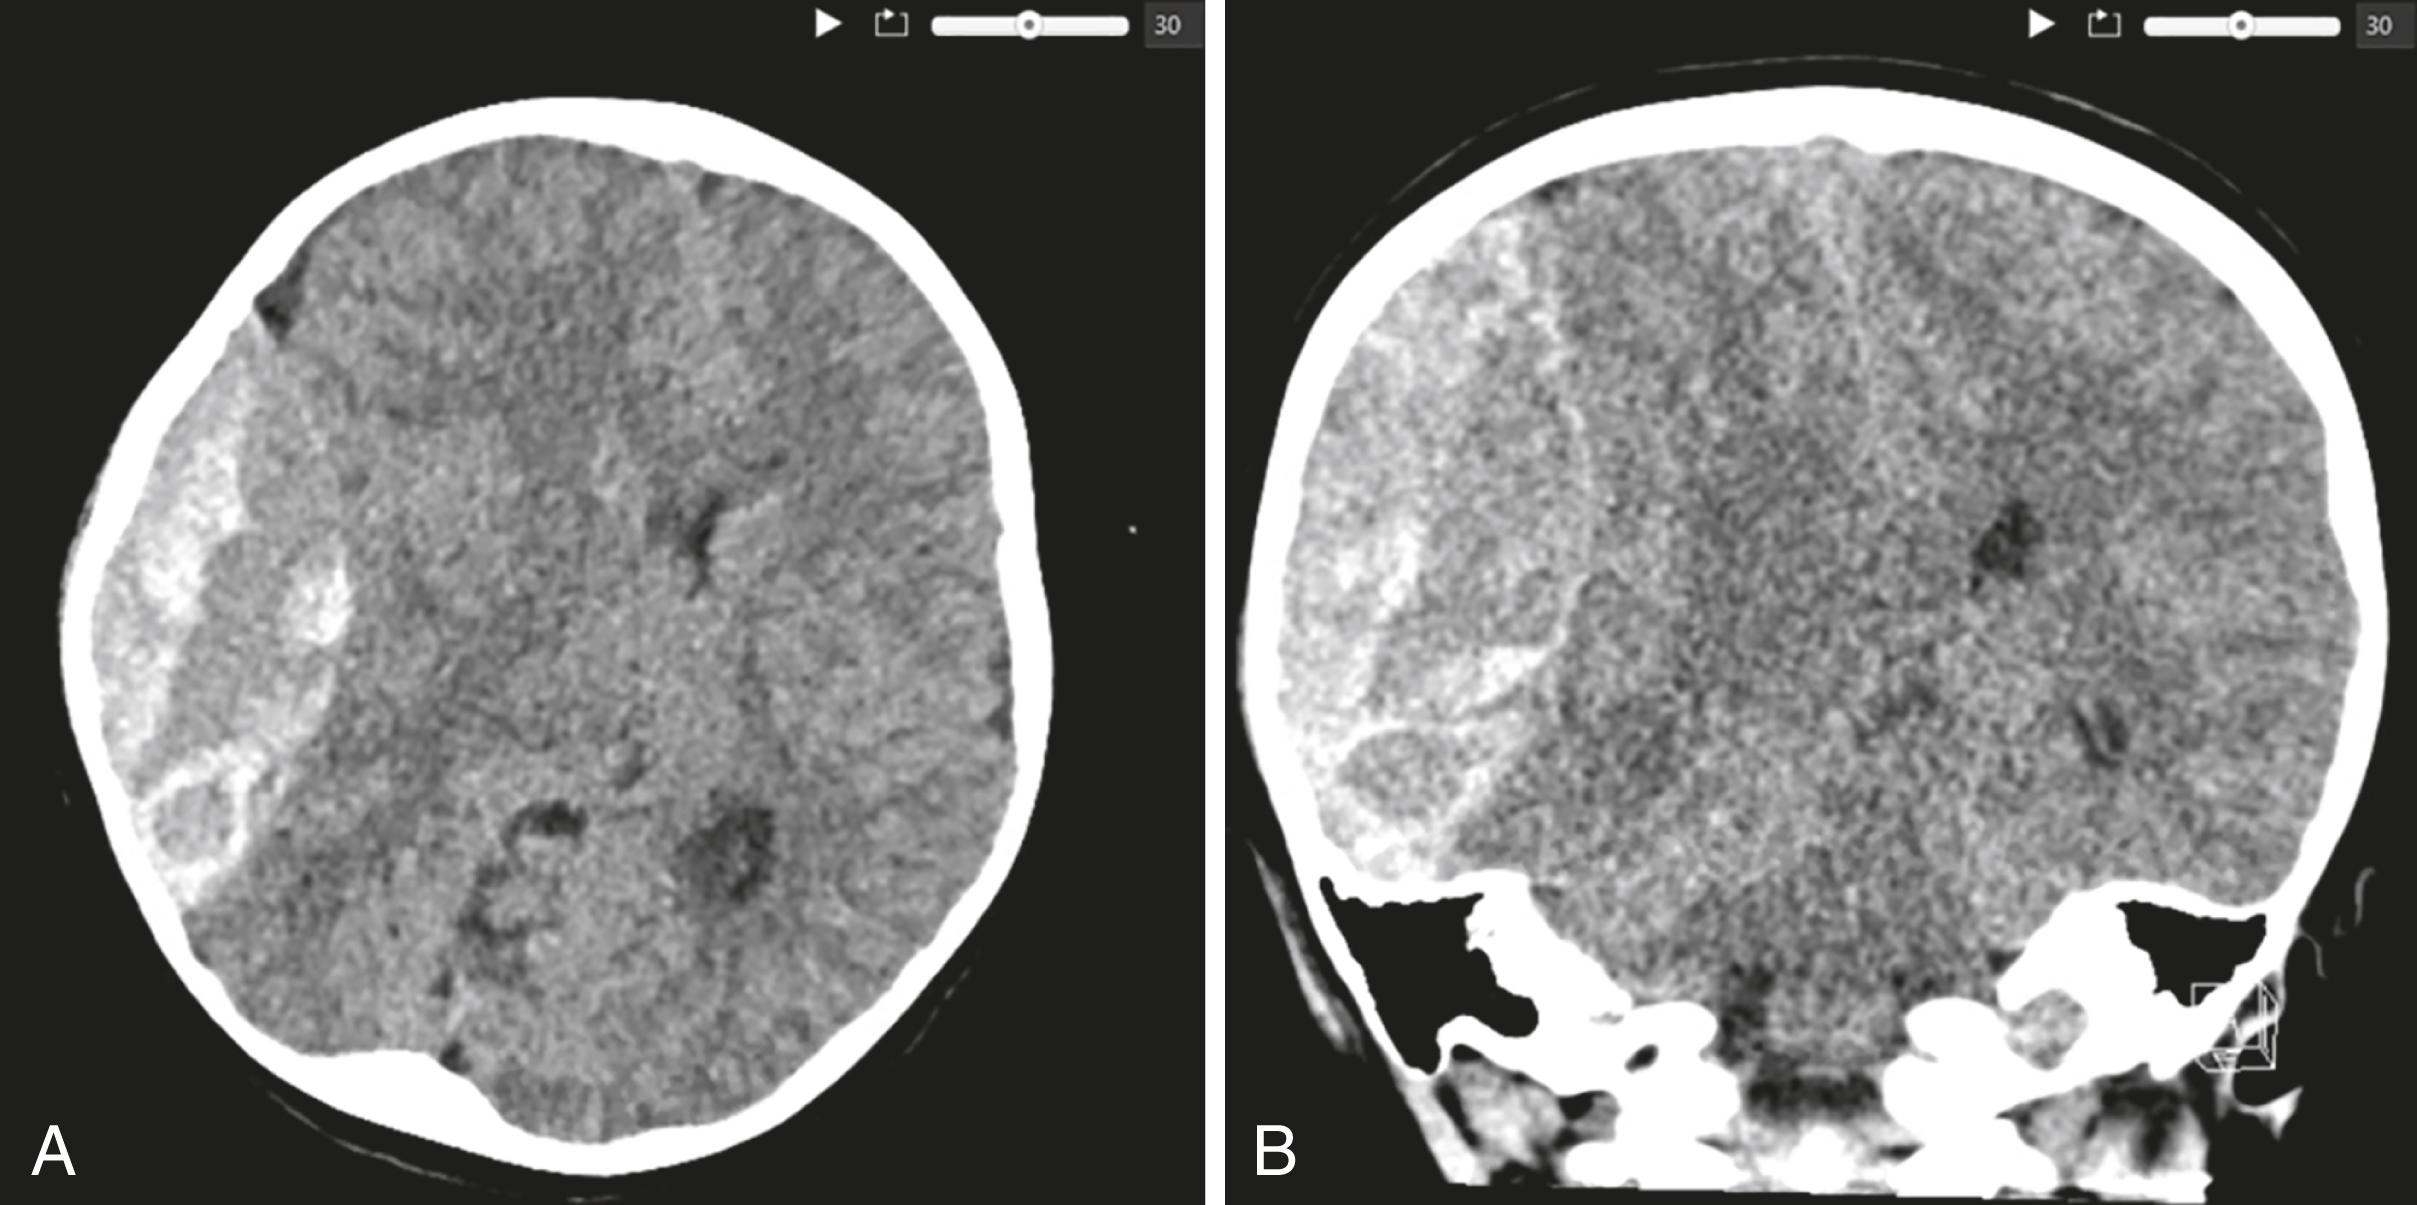

Figure 1.1, Head CT without contrast axial (A) and coronal (B) views demonstrate a large 8.5 cm right parietal epidural hematoma with 1 cm midline shift. Note the ominous “swirl sign” or areas of hypodensity in the hyperdense clot, which is concerning for active extravasation.